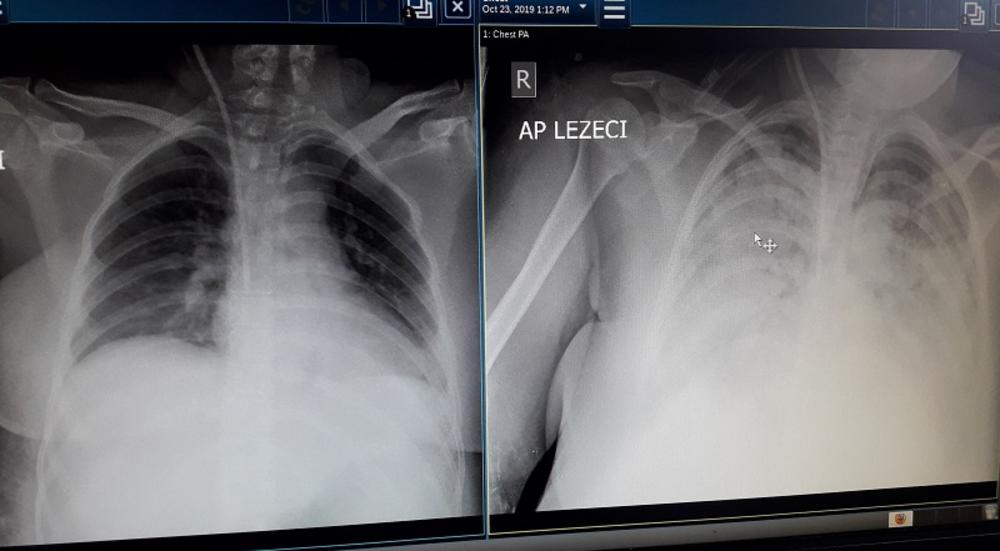

Nejmi je u šestoj nedelji trudnoće na jednoj privatnoj klinici u Novom Pazaru prošlog petka iz materice odstranjen mrtav plod i nakon toga počinje njena drama. U opšte lošem stanju sutradan je primljena u bolnicu u tom gradu, ali njen organizam na lečenje nije dobro reagovao. Naprotiv. Stanje se progresivno pogoršavalo i nakon ustanovljene teške sepse u nedelju je hitno transportovana u Urgentni centar kragujevačkog Kliničkog centra. Normalne vrednosti krvnog pritiska i trombocita nisu mogle da se održe ni na koji način, dramatično su se povećavali parametri zapaljenja. Klinička slika u naredna 24 časa očekivano se produbila, jer se sepsa odlikuje popuštanjem sistema vitalnih organa. Iz minuta u minut opadale su apsolutno sve funkcije u organizmu potrebne za život: kardiovaskularna, respiratorna, bubrežna, sistem zgrušavanja krvi... Izostajao je efekat primene moćnih lekova u najvećim dozama, priča nam dr Vukićević.

Urgentni centar je doslovno regrutovan - okupio se veći broj specijalista, pre svega anesteziologa, nefrologa, hematologa, ginekologa, farmakologa... Angažovani su svi resursi dostupni u najsavremenijim medicinskim ustanovama u svetu i u našoj zemlji, pre svih vantelesna podrška organima i odstranjivanje štetnih materija i toksina nastalih u ovoj teškoj infekciji, uz najviši nivo suporativnog lečenja, odžavanja vitalnih funkcija, antibiotici u udarnim dozama... Nejma je za pet dana primila toliku količinu krvi za koju je potrebno 40 davalaca, pa lekari ovom prilikom naglašavaju kolika je važnost dobrovoljnog davalaštva za spasavanje ljudskog života.

Jedna od ključnih stvari za njeno preživljavanje bila je upravo primena vantelesne (ekstrakorporalne) podrške organima, metode koja se koristi kod najkritičnijih pacijenata, gde je potrebno istovremeno održavati funkcije apsolutno svih vitalnih organa. Tu su ključnu ulogu odigrali dr Tatjana Lazarević i dr Zoran Kovačević, koji su, sa timom tehničara Odeljenja dijalize i Urgentnog centra, danonoćno pratili kliničke i laboratorijske parametre, korigovali terapiju. Reč je o kompleksnoj metodi koja se više od deset godina primenjuje u KC Kragujevac i omogućava natežim, životno ugroženim bolesnicima, da se oporave i prežive.